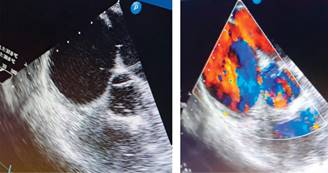

Se realiza ECOTT en donde informan: dilatación de cavidades derechas, con datos de hipertensión pulmonar (100 mmHg). Se integra diagnóstico de SE. Flujograma transmitral no valorable por fusión de ambas ondas. Se realizó maniobra de contraste salinado, se observa paso inmediato y al primer latido de la aurícula derecha a la aurícula izquierda, sin poder caracterizar el tipo de comunicación o shunt intracardiaco. Se inicia manejo con análogos sintéticos de prostaciclina.

Se realiza ecocardiograma transesofágico, el cual señala: defecto del septum interauricular tipo ostium secundum amplio de 17 mm con flujo bidireccional (Figura 3).